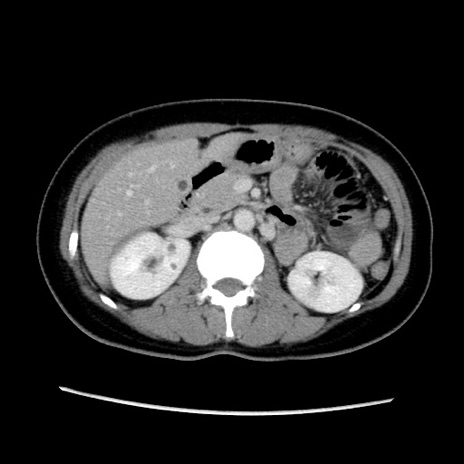

症例39(横断像)

【症例】40歳代女性

【主訴】上下腹部痛

【現病歴】2日目から下腹部痛あり。夜間は痛みで眠れなかった。昨日より上腹部痛と下痢が出現。臥位で痛みは軽快したため、休んでいた。本日になって臥位でも立位でも痛みが強くなってきたため救急要請。

【既往歴】子宮内膜症

【身体所見】部:平坦・軟、左上下腹部に圧痛あり、反跳痛あり。

【データ】WBC 21800、CRP 26.78